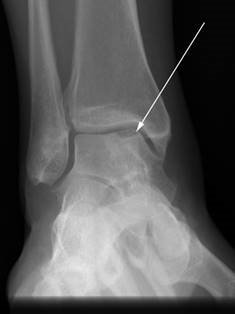

Weight-bearing anteroposterior (AP), lateral, and sesamoid axial radiographs are mandatory. On the AP view, the surgeon measures the Hallux Valgus Angle (HVA, normal < 15°), the Intermetatarsal Angle (IMA, normal < 9°), and the Distal Metatarsal Articular Angle (DMAA). The lateral view is scrutinized for Meary's angle (talo-first metatarsal angle) to identify midfoot collapse, as well as the presence of dorsal osteophytes indicative of hallux rigidus. The sesamoid axial view is critical for assessing the degree of sesamoid subluxation and the integrity of the crista.

Clinical & Radiographic Imaging Archive